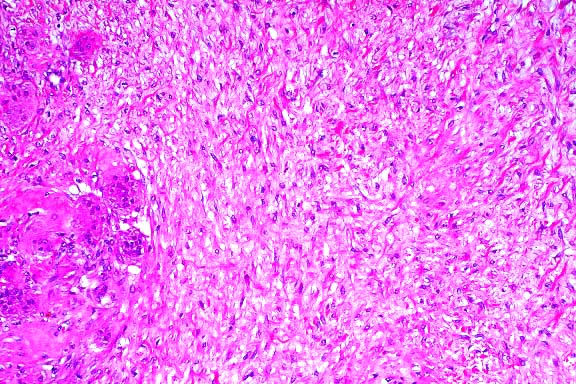

Early lesions appear histologically as multifocal subcutaneous

accumulations of amorphous lightly basophilic material which

is periodic acid-Schiff positive, stains brown with acid orcein

Giemsa, and can be shown by von Kossa stain to contain calcium.

Within the basophilic material, hemorrhage is occasionally seen,

and fractures or fissures are seen commonly, but inflammatory

and fibroplastic responses are negligible. Intermediate lesions

are more likely to have fully mineralized areas within the amorphous

material, which is surrounded by mild to moderate granulomatous

inflammation and fibroplasia. Late lesions are associated with

marked granulomatous inflammation and fibroplasia, with macrophages,

multinucleate giant cells, lymphocytes, and a few plasma cells

and neutrophils. Inflammatory cells are arranged around mineralized

centers in palisading granuloma fashion. Although these centers

are generally acellular, they do incorporate some macrophages,

fibroblasts, and histiocytic giant cells containing phagocytized

mineral. Granulomatous areas are separated by thick connective

tissue septa. Cartilaginous or osseous metaplasia is seen in

56.9% of late lesions. Very old lesions are multilocular, with

thick connective tissue trabeculae, and are characterized by

completely mineralized areas without much active inflammation.

- Case 20-4. Cervical vertebra. Multifocally areas of

endochondral bone partly replaced by granular mineralized debris

are surounded by macrophages, foreign body giant cells, and fibrous

connective tissue.